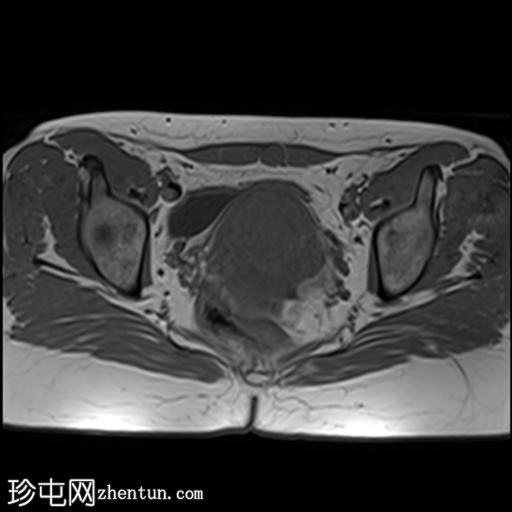

轴位

T1加权像

子宫增大,前倾后屈,可见多发大小不一、位置各异的壁内肌瘤(主要位于Figo 2、5和6区)。

一个边界清晰的带蒂宫腔内肿块经扩张的宫颈管脱出。T1加权像上呈等信号,T2加权像上呈中低信号,周围环绕着高信号的子宫内膜,静脉注射对比剂后呈明显不均匀强化。

双侧卵巢外观正常,可见小卵泡。